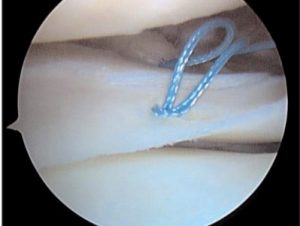

Σε περιφερικές ρήξεις που υπάρχει σχετική αιμάτωση και αγγείωση στον μηνίσκο κυρίως σε νέα άτομα κάτω των 35-40 ετών γίνεται προσπάθεια συρραφής του μηνίσκου.

Επίσης σε αποσπαστικη ρήξη ρίζας οπισθίου κέρατος μηνίσκου ( meniscal root tear) σε σχετικά νέα άτομα γίνεται αρθροσκοπική συρραφή και σταθεροποίηση.